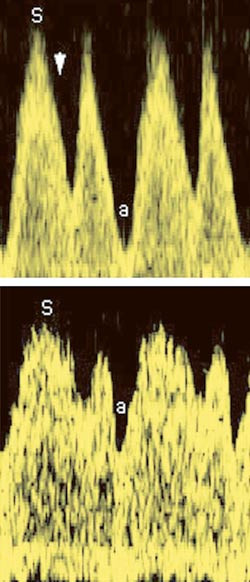

Pasient 3. En gravid kvinne ble syk i 12. svangerskapsuke med feber, utslett og senere leddsmerter. I serum fra mor ble det etter hvert påvist IgG- og IgM-antistoff mot parvovirus B19, forenlig med aktuell infeksjon. Da hun i 25. svangerskapsuke kjente mindre liv, ble hun utredet nærmere og fikk påvist føtal ascites (fig 1), subkutant ødem, placentaødem, leverforstørrelse, intrakraniale forandringer forenlig med hjerneødem, ekkogene nyrer og tom urinblære. Kardiomegali, perikardeffusjon, lekkasje gjennom mitral- og trikuspidalklaffen og økt pulsatilitet i prekordiale vener tydet på hjertesvikt (fig 2). Forhøyede blodstrømshastigheter i a. cerebri media tydet på anemi. Blodprøve fra navlesnoren bekreftet anemi (Hb 1,9 g/100 ml) og trombocytopeni (Trc 17 · 10⁹/l). Fosteret fikk transfusjoner, men døde. Underveis hadde det utviklet seg ventrikkelseptumdefekt (fig 1). Parvovirus B19-DNA ble påvist ved polymerasekjedereaksjon i fosterblod, fostervann og placenta samt i mors serum.

Siden tilstanden kan behandles, bør det ved kjent eller mistenkt eksposisjon utføres serologisk diagnostikk av gravide kvinner. Deteksjonsraten med denne metoden er 81,3 % (14, 15). Dersom IgM-antistoff mot parvovirus B19 påvises, er dette tilstrekkelig grunnlag for henvisning til spesialavdeling. I føtalt blod er sensitiviteten av serologiske undersøkelser lav (43,8 %). Dopplermålinger i fosterhjerne, hjerte, ductus venosus, umbilikalvene og -arterie gir en oversikt over fosterets sirkulatoriske situasjon og kan avdekke anemi (16, 17), myokardaffeksjon og portahypertensjon (18). Påvisning av parvovirus B19-DNA med polymerasekjedereaksjon er en sensitiv metode og kan utføres i mors blod, fostervann, placenta eller navleveneblod. På grunn av risiko for komplikasjoner vil kordocentese vanligvis bare bli gjort i tilfeller der det er berettiget mistanke om anemi.

I de tilfellene der mor er smittet, men hvor det ennå ikke er symptomer hos fosteret, vil gjentatte dopplerundersøkelser kunne indikere lavt hemoglobinnivå før hydrops utvikles.